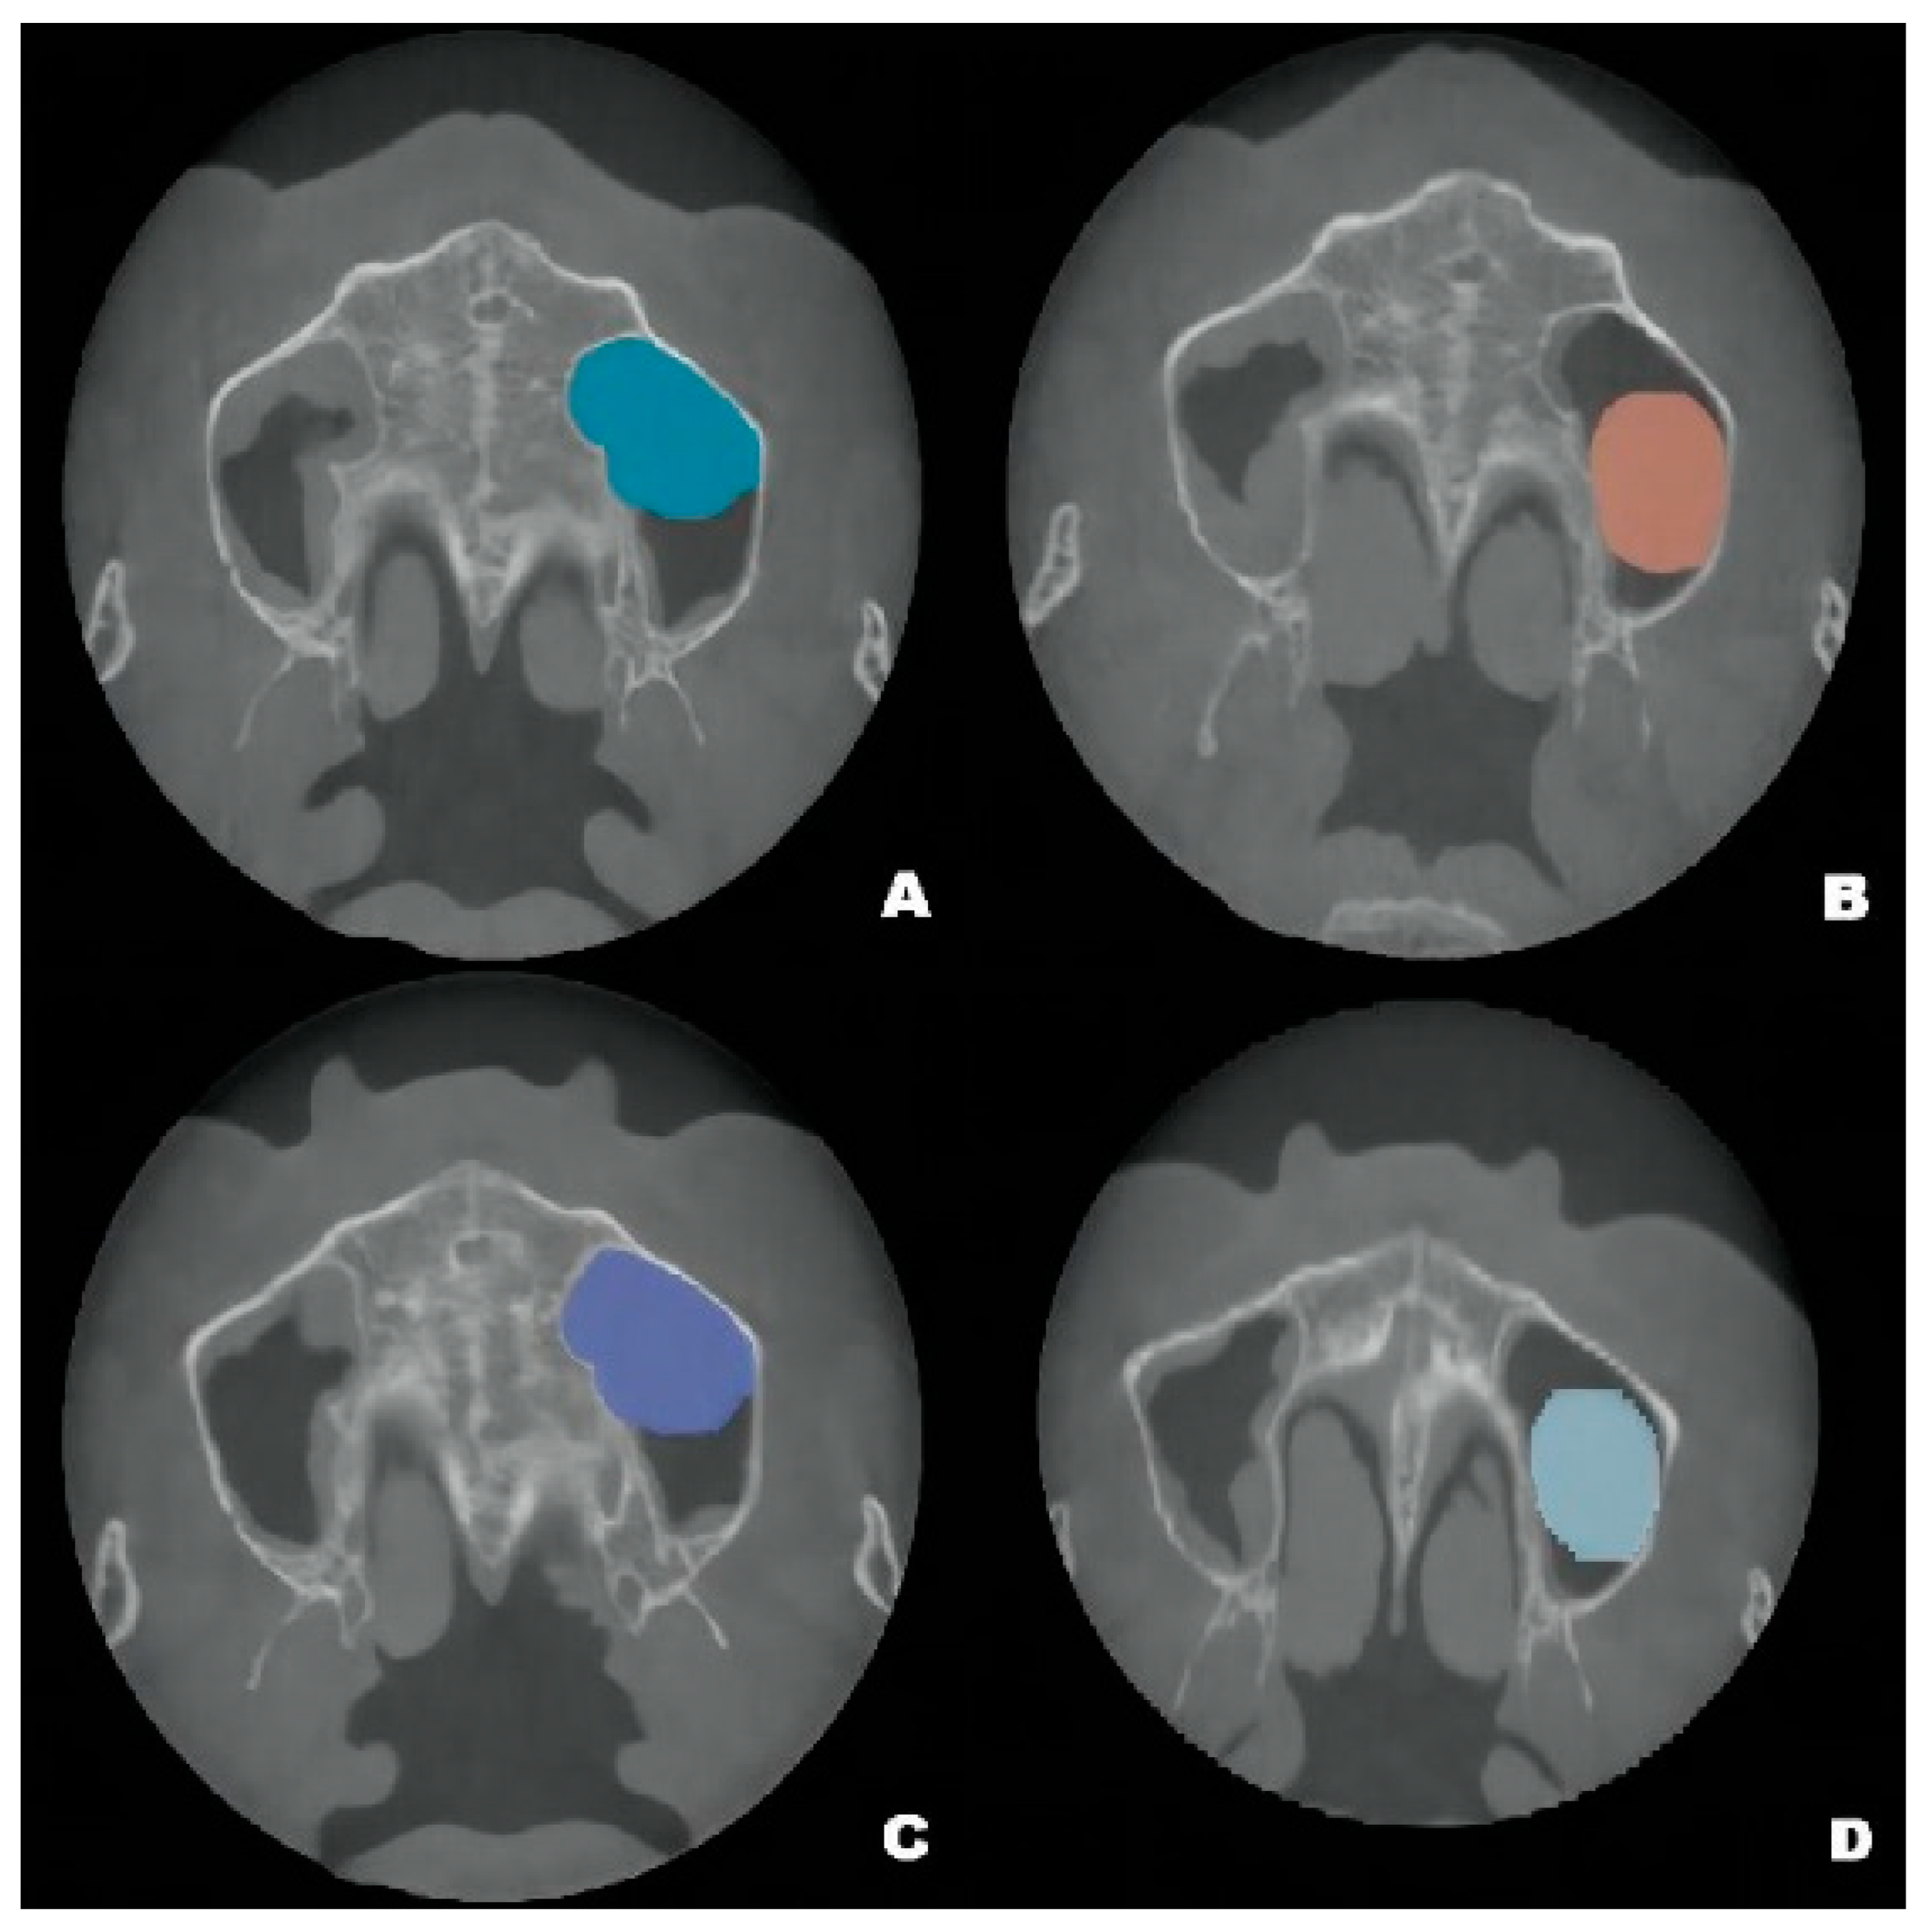

Figure 2.

The volume changes and maximum diameter changes in the axial, coronal and sagittal planes of the patient’s left maxillary antral pseudocyst in the preoperative CBCT image (A) and the follow-up CBCT examinations in 6 (B), 12 (C) and 22 months (D), respectively.

The pseudocyst volume was manually segmented using 3D Slicer and corrected by a professional radiologist [19]. Measurements of the maxillary sinus pseudocyst revealed that its volume decreased from 3.795 mm3 before surgery to 2.370 mm3 at 6 months post-surgery; it gradually returned to the preoperative volume at 12 months (3.439 mm3), then decreased to 2.930 mm3 at 22 months (Figure 2).

CBCT examinations were performed on CBCT scanners (3D Accuitomo, J. Morita Mfg. Corp., Kyoto, Japan) using the following parameters: 85-kV tube voltage, 5.0-mA tube current, field of view of 100 mm × 50 mm, and slice thickness of 1.0 mm. Dental CBCT scans showed that the local alveolar ridge width was optimal (8.688 mm for the left maxillary second premolar and 10.130 mm for the first molar) (Figure 1B,D); however, sinus augmentation was needed because the height of the residual alveolar bone in the posterior maxillary area was insufficient for implant placement. The patient was observed to have type 3 bone quality in the posterior maxilla on both sides, and according to our observation, there was no obvious thickening of the nasal mucosa in the pre-operative CBCT image. Notably, the height of the crestal bone between the sinus floor and the alveolar ridges of the left maxillary second premolar and first molar were 8.688 mm and 4.385 mm, respectively (Figure 1A,C). CBCT also revealed a homogeneously opaque, dome-shaped, and well-delineated lesion (volume, 3.795 mm3) in the left maxillary sinus (Figure 1 and Figure 2A); the lesion did not exhibit an epithelial lining. Prior to attending our clinic, the patient had consulted an otolaryngologist and received confirmation that no mucous cyst was present (no aggressive lesion appearance, significant bone resorption, or invasion of adjacent structures observed on radiologic imaging). Because the patient did not exhibit relevant symptoms, the otolaryngologist suggested conservative management of the pseudocyst. Accordingly, the treatment plan comprised osteotome sinus floor elevation, with simultaneous implant placement on the left side, in the presence of an antral pseudocyst.